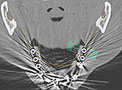

実際にCTで撮影し、「CTデータ3D立体構築画像変換検査」したものがどう見えるのがご覧下さい。CTデータ3D立体構築画像変換検査した場合、3次元でどこにどのようにインプラントを埋め込んでいけばいいのか、立体的に把握することができます。

CTデータ3D立体構築画像変換検査は患者さまの顎の骨や歯の状況を立体的に把握します。あらゆる角度から検討でき、インプラントの植え込み位置、角度などの事前シミュレーションが的確に行われ、数値化することができます。

CT撮影だけを行い、インプラント治療に臨む医院さんの場合、通常のCTでは数ミリの空洞をも見つけることはできません。そのため失敗に終ることがあるのです。

「当院ではインプラント治療の際にCTを撮影しています」といううたい文句もよく見かけますが、それだけでは不十分であるといえます。

インプラント手術を行う前には、CTデータ3D立体構築画像変換検査で血管・神経の正確な位置の把握とばい菌の塊の位置などについても把握する必要があります。

今まで合っていない入れ歯を使い続けたり、今まで受けた様々な歯科治療の結果、顎の骨の形がいろいろ変形し、ある部分は尖り、ある部分は陥没し、また、顎の左右や前後の骨のボリュームが違っていたり、また、顎の骨から神経の出てくる穴の位置を確認したりするために、CTスキャナーを用いて、顎の骨を立体で観察・診断します。

CTスキャナーで撮影すると、手術をし、歯茎を開いたあとの様々な問題をあらかじめ把握する事ができます。